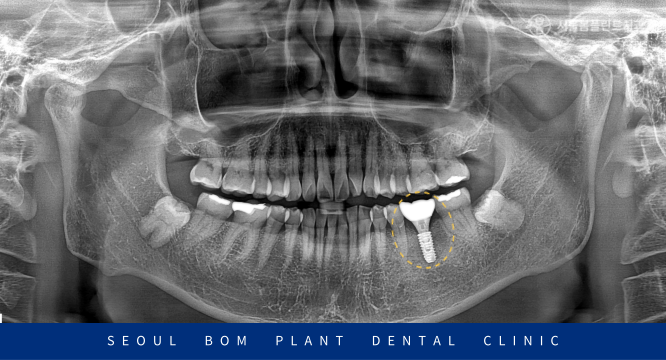

방이역치과 서울봄플란트치과는

식립 전 3D-CT를 통해

육안상 확인하기 어려운 혈관 및

아래턱 하방으로 지나가는 큰 신경관인

하치조 신경관의 위치 등

해부학적인 구조를 정밀하게 파악합니다.

그 후 임플란트가 식립 될 위치와 방향 등

사전에 계획을 꼼꼼히 세운 후

안정적으로 과정을 이어가고 있습니다.

염증으로 인한 치조골 소실이 심해

치조골 이식술을 동반하여

임플란트 식립을 안정적으로 도와드렸습니다.

임플란트 식립 후 충분한 시간이 지난 뒤

Osstell beacon이라는 장비를 이용하여

ISQ(골유착정도)를 측정하여

안정적인 수치를 확인해주고

최종 보철물 수복을 진행하였습니다.